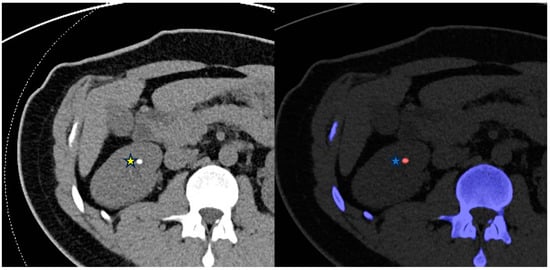

5.3. Examples in the Biliary System

5.3.1. Cholelithiasis

5.3.2. Cholecystitis